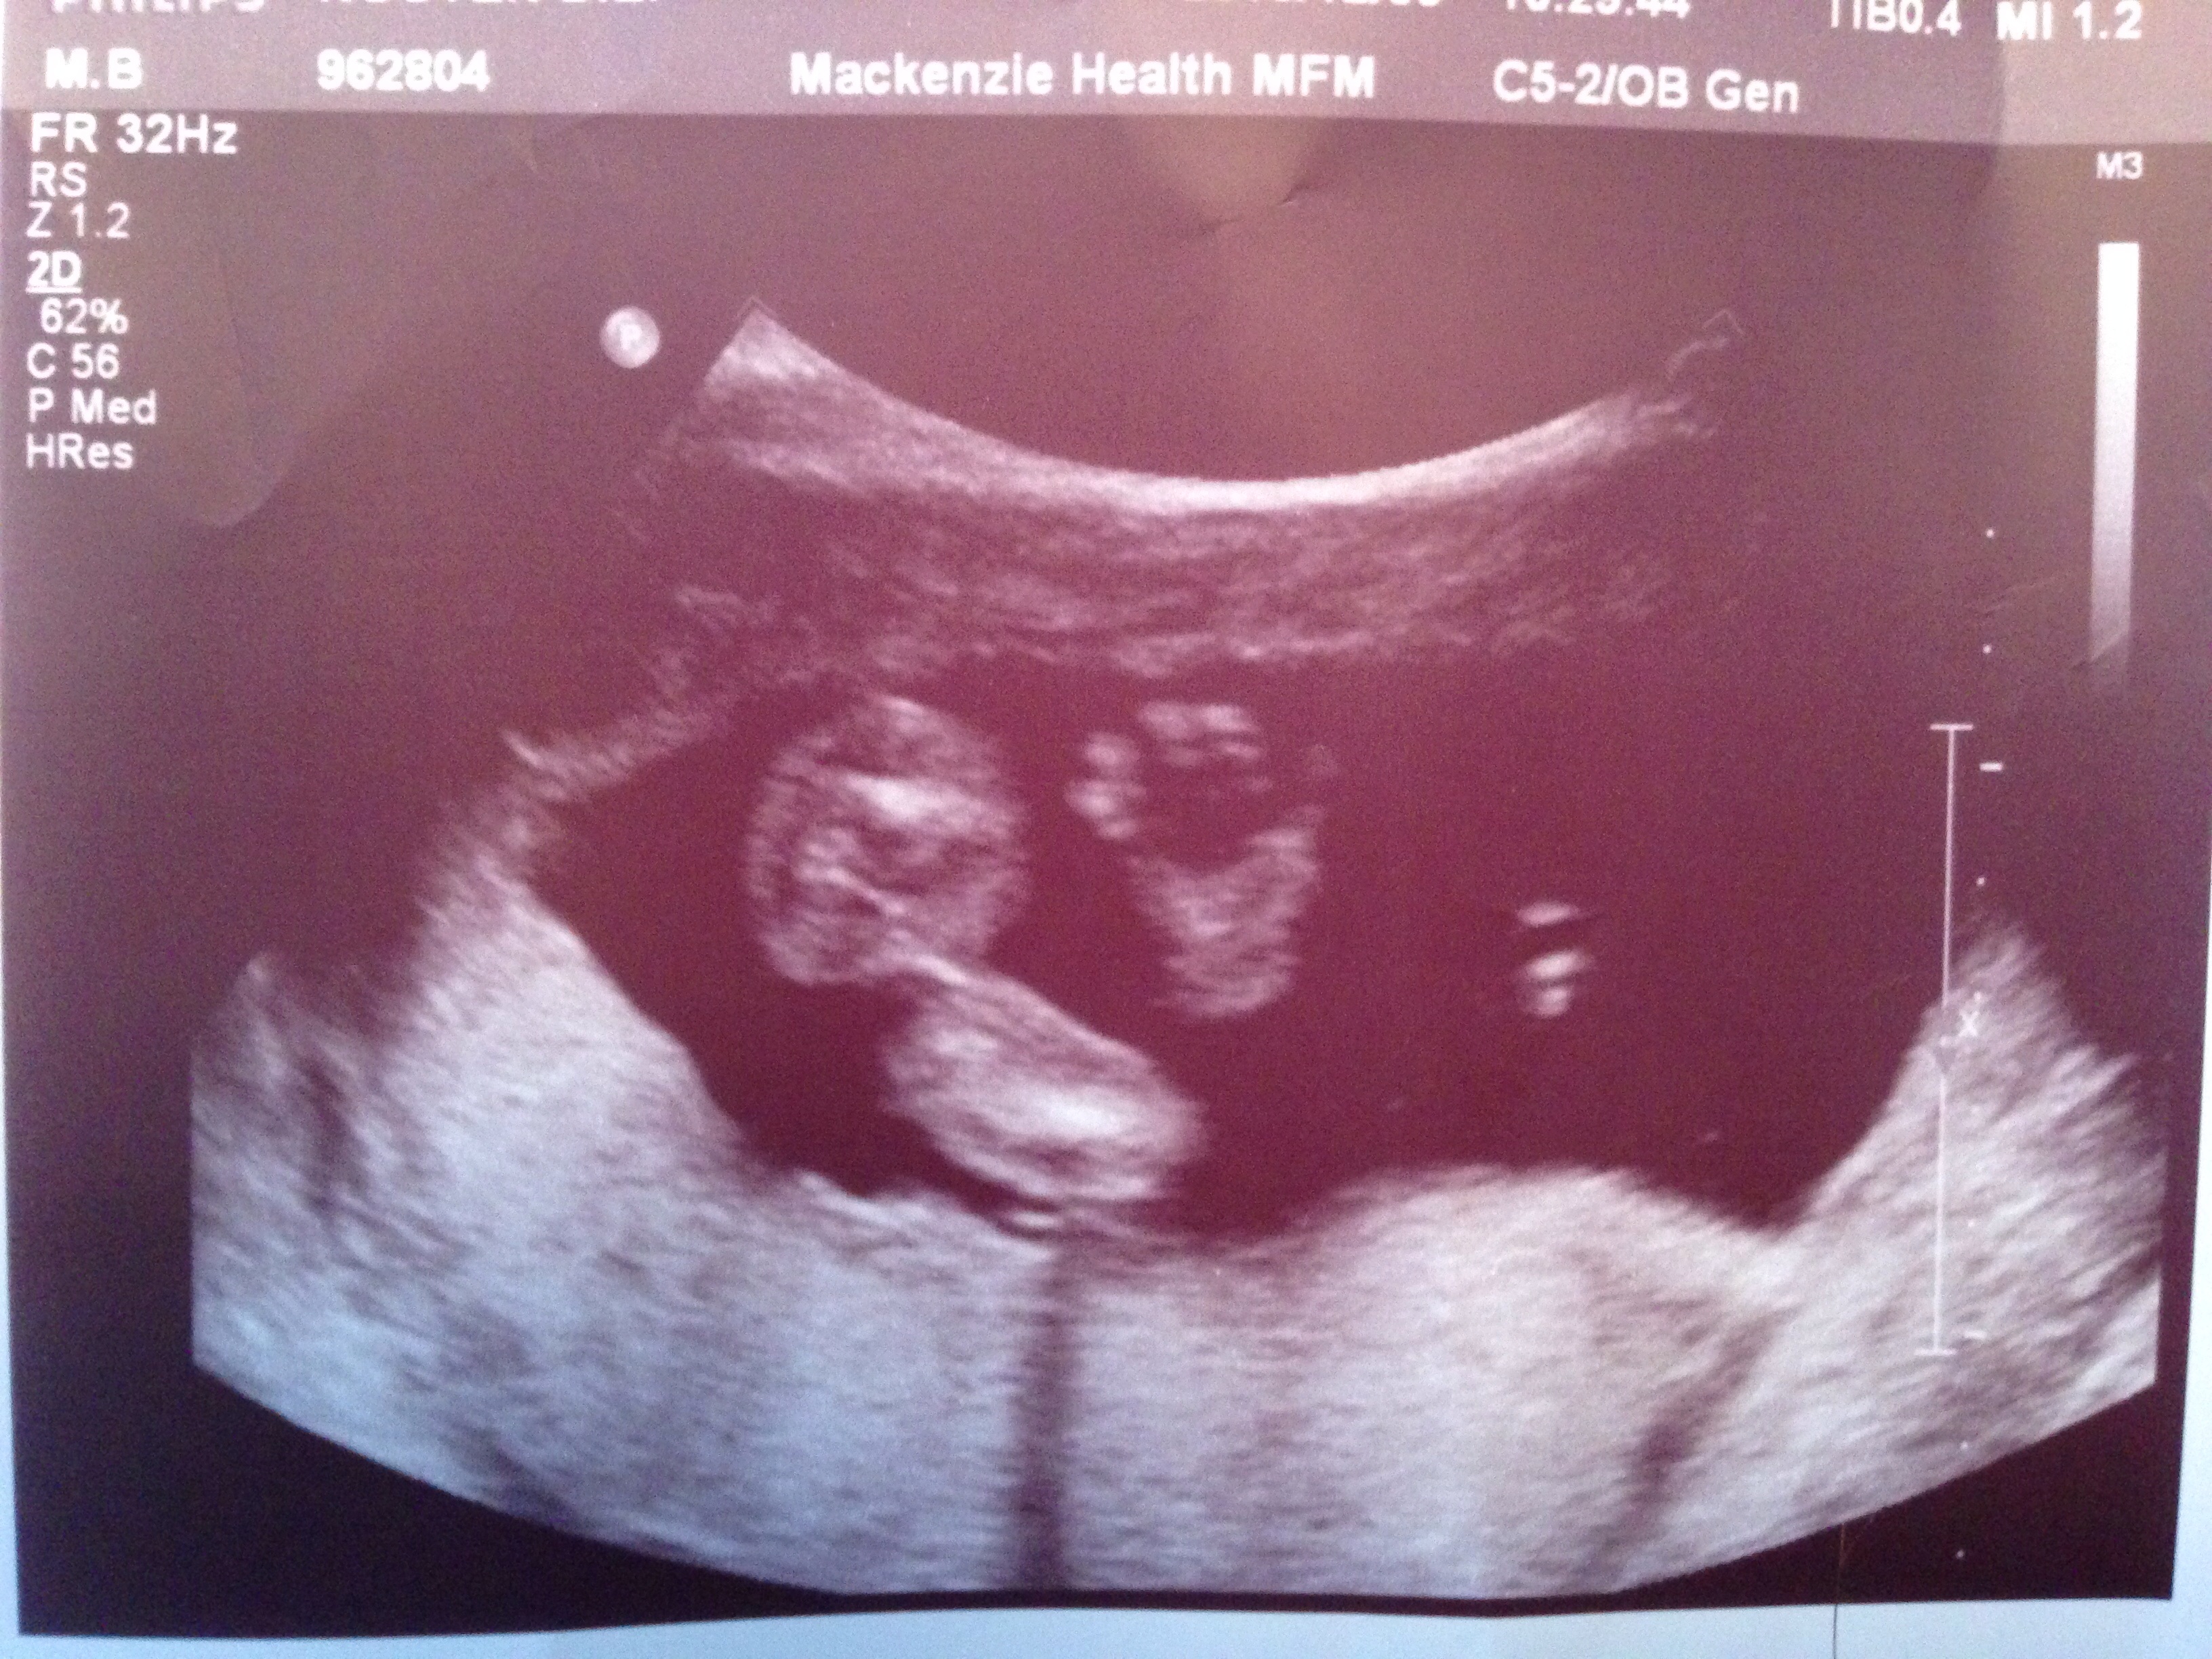

UPDATED through 12/6: Week of 12/2 Anatomy Scan

Re: UPDATED through 12/6: Week of 12/2 Anatomy Scan

• Ours is Wednesday the 4th.  Getting SO excited.

• Congrats everyone on your healthy babies!! How have I only just seen this?? I have my scan on the 3rd :-D excited!!